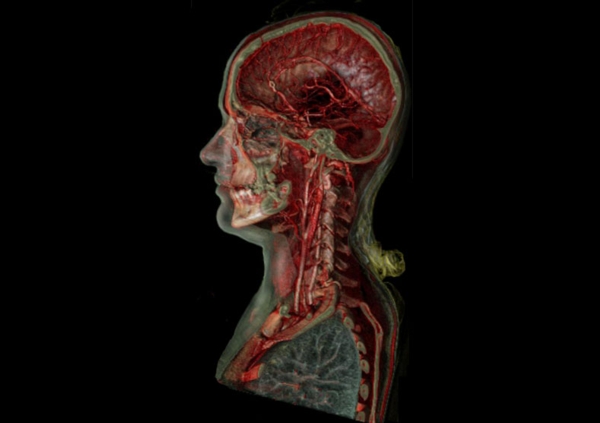

在随后的幻灯片中,您将看到来自瑞典医学图像科学与可视化中心(the Center for Medical ImageScience and Visualization ,CMIV)的Anders Persson和他的同事们运用CT,MRI和超声得到的令人惊叹的尸检图片。这些图片描绘了人体骨骼,消化道,循环系统和大脑以及野猪的前端结构。

8, 人体,侧切面;肩部以上血管的空间结构清晰可见。